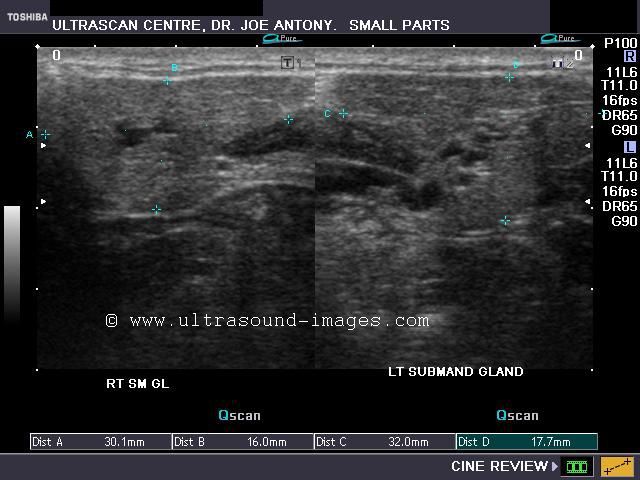

A) Submandibular salivary glands

The above ultrasound images of the normal submandibular salivary glands show homogenous echotexture and fine soft tissue echogenicity. The color doppler image shows the gland to be vascular. Echogenicity appears slightly less than that of a normal thyroid gland.